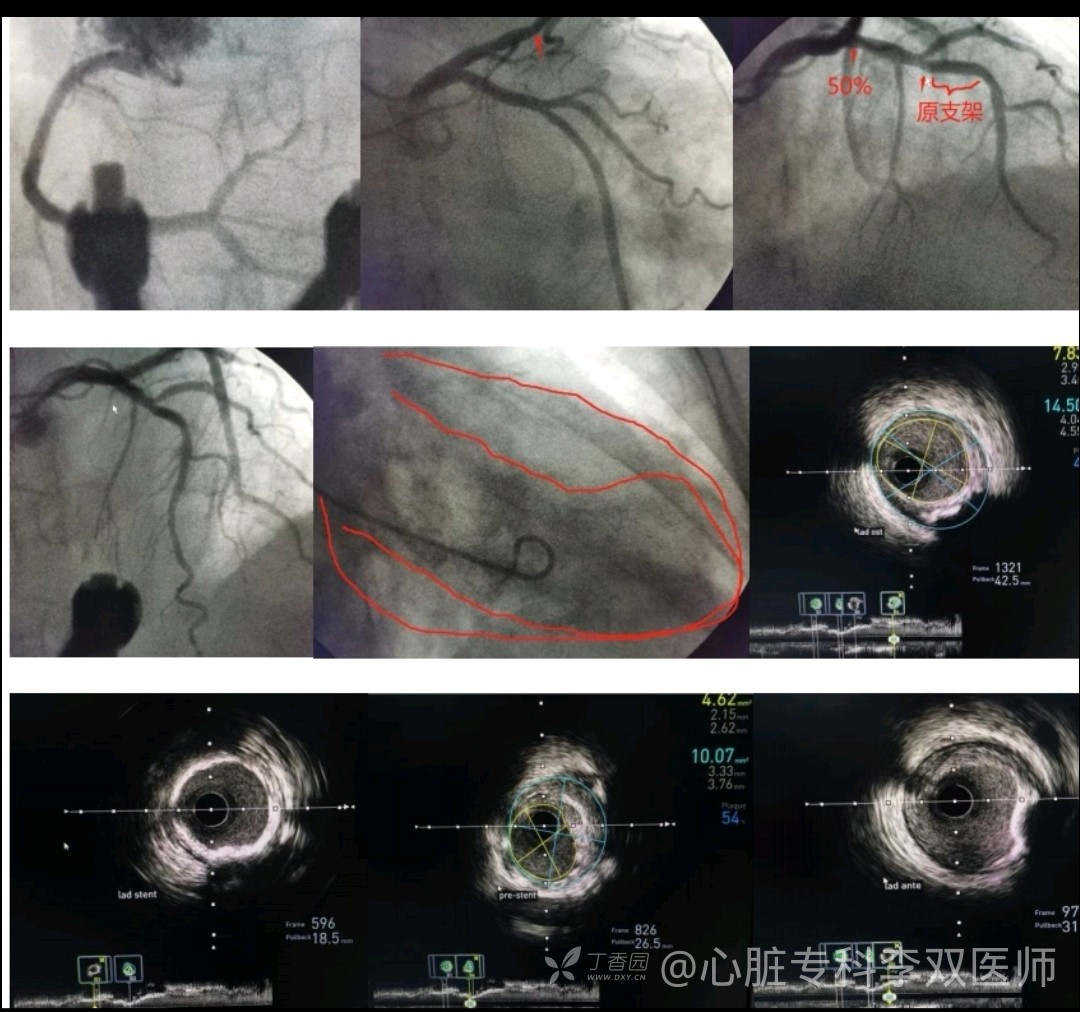

我们会诊考虑确实不能排除心梗,当时做了急诊冠脉造影,不是心梗!(彩超没有报室壁瘤,不过它也排除了血栓,所以才敢打心室造影的)。

心尖部大室壁瘤引起的前壁和侧壁ST抬高,推测患者20年前放支架是急性前壁心梗。